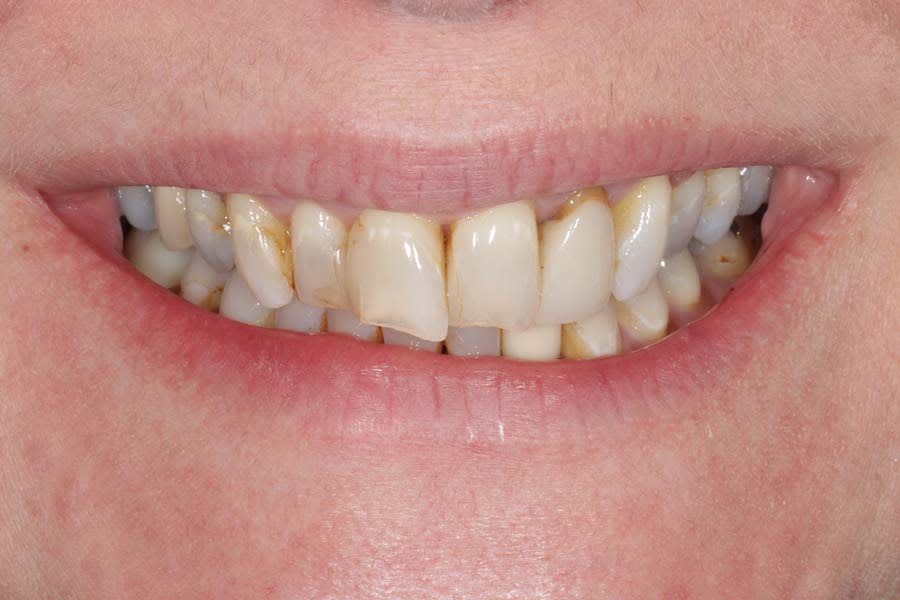

The patient expressed worry about further tooth fractures and dissatisfaction with anterior tooth wear and chipping (Figure 1 and Figure 2). She sought esthetic smile improvement and a comprehensive plan to prevent further breakdown and was open to a systematic approach to data gathering for diagnoses and planning. Historically reliant on single-tooth dentistry, she embraced a thorough approach that involved orthodontics and restorative care to address occlusal and esthetic issues.

Dentofacial: The patient expressed concerns about mismatching tooth color, shape, and position. Her lip moved 10 mm from repose to Duchenne smile, placing her in the high end of normal range (6 mm to 10 mm).3 Gingival margins were uneven with supraeruption present resulting in a diagnosis of dentoalveolar extrusion with wear.4 Tooth rotations and overlaps were present as was a “black triangle,” ie, missing papilla, between teeth Nos. 9 and 10 due to the 6.8 mm distance between the crestal bone and contact point (Figure 7 and Figure 8).5 Pronounced negative buccal corridors were evident. Gingival tissue was displayed while smiling, giving the patient a high-risk dentofacial diagnosis.